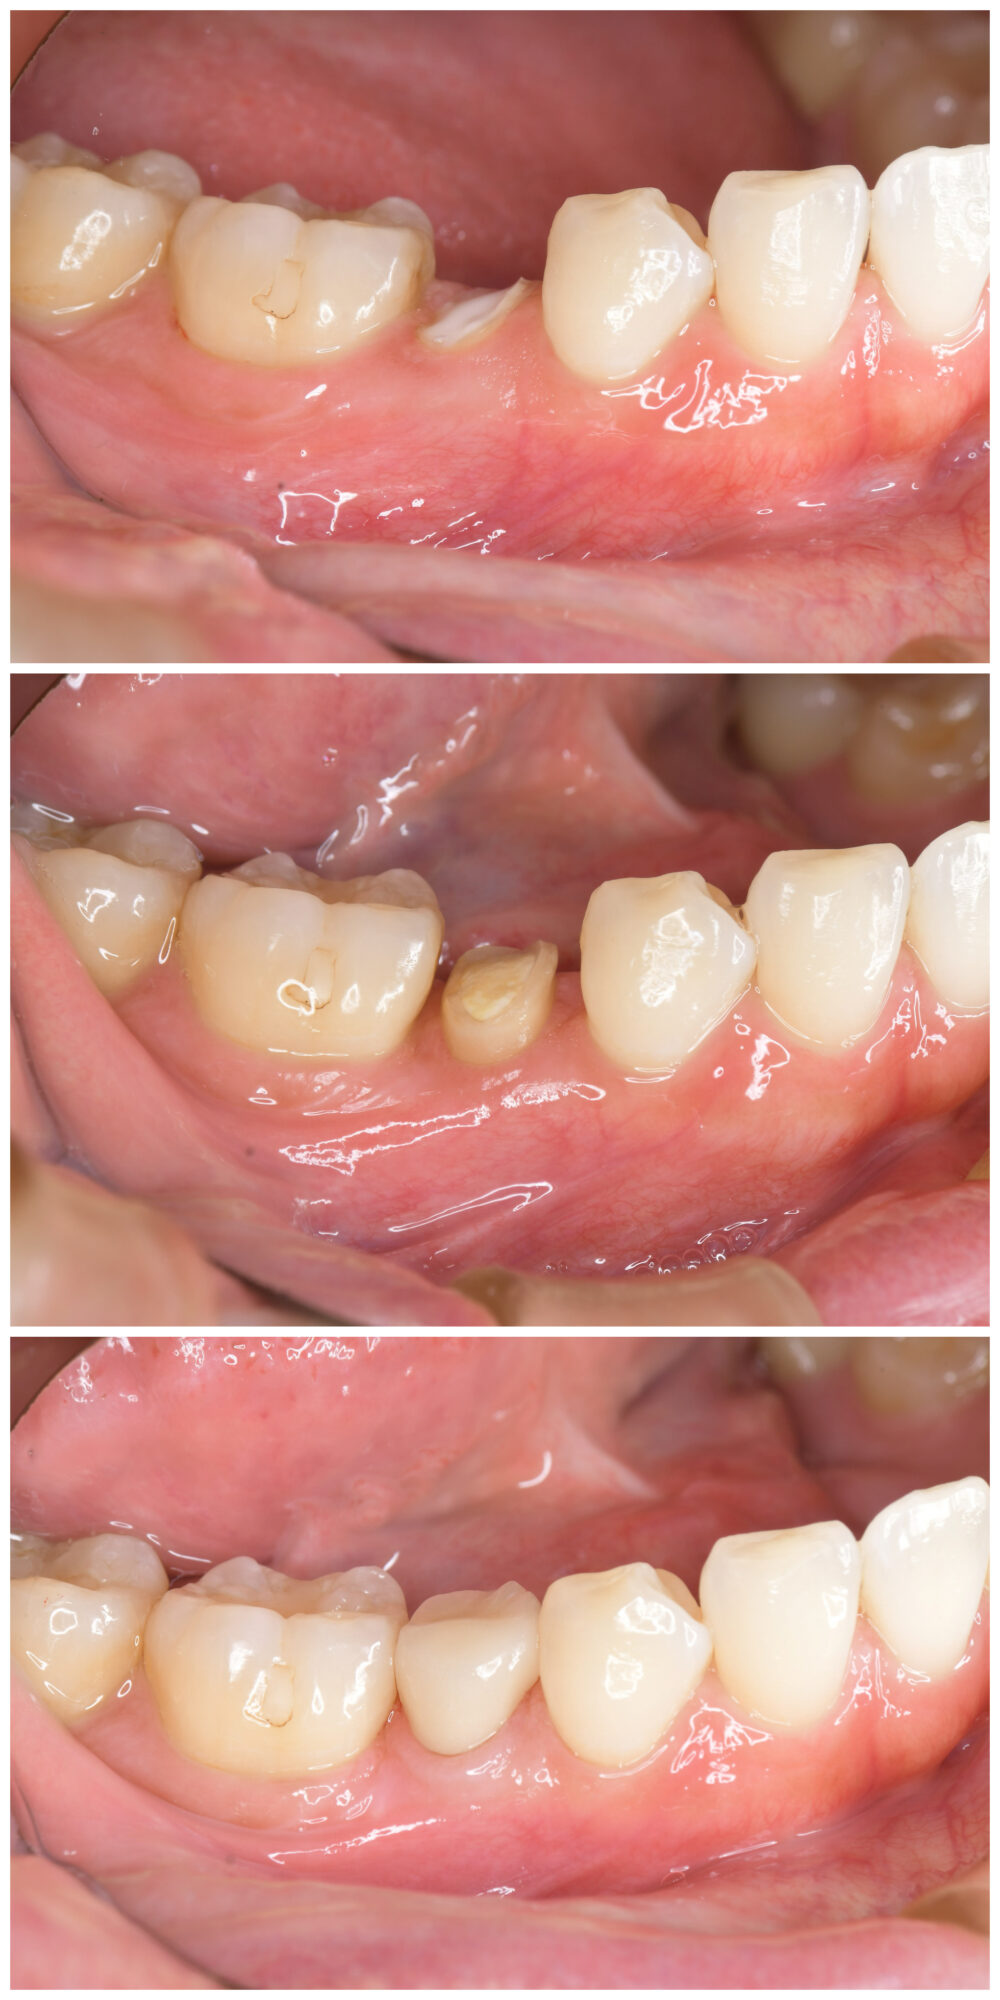

移植前

重度虫歯の右上6番の歯に、右上の親知らず(8番目)を移植しました。

移植後